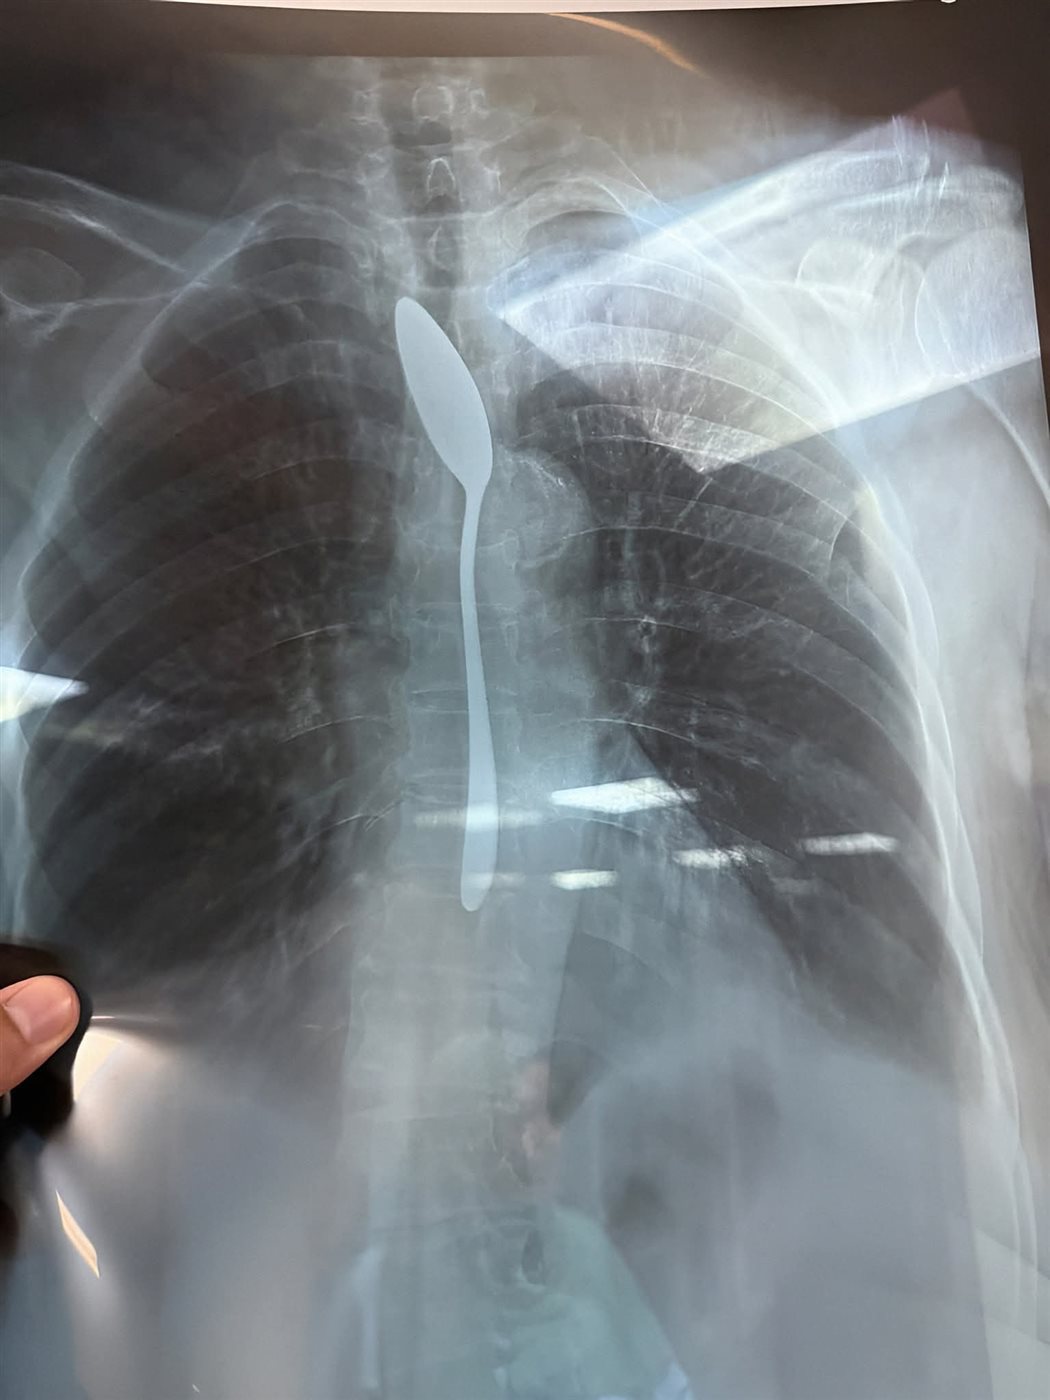

وبحسب مصادر طبية من داخل المستشفى، فقد شك الفريق في صحة الرواية في البداية نظرًا لصعوبة ابتلاع جسم معدني بهذا الحجم لدى سيدة مسنّة، إلا أن نتائج الأشعة أكدت المفاجأة، حيث أظهرت صورة واضحة لملعقة شاي كاملة مستقرة داخل المريء، مما استدعى تدخلا عاجلًا لإنقاذ حياتها.

وعلى الفور، تم تجهيز المريضة داخل غرفة العمليات واستدعاء الاستشاري المختص، حيث جرى استخراج الملعقة عن طريق منظار المريء في زمن قياسي لم يتجاوز من 5 إلى 7 دقائق، وسط حالة من الترقب داخل غرفة العمليات. وتمت العملية بنجاح كامل دون أي مضاعفات، وسط فرحة كبيرة بين أفراد الفريق الطبي وأهل المريضة.